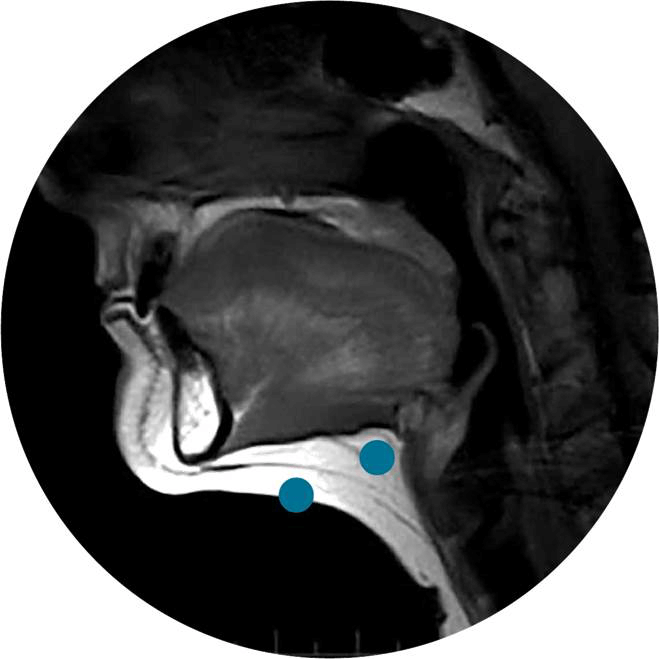

大部分萬惡的雙下巴都是這一型。下巴的脂肪分成頸闊肌前側 (pre-platysma) 和頸闊肌後側 (post-platysma) 兩部分,當我們做出咬牙切齒的動作時,頸闊肌會出力把前側的脂肪向外頂出,這時用手指輕捏就能測出脂肪的厚度。頸闊肌前側脂肪是造成肥厚下巴的主因,可以使用倍克脂 (Belkyra) 和電波拉提 (Thermage) 來治療,而後側脂肪則不建議處理,否則容易造成過度凹陷,影響外觀。

(圖片來源From ultherapy.com)

還有一些情形會讓下顎看起來有點臃腫,如頷下腺肥大 (submandibular gland hypertrophy) 或淋巴腫大,這些狀況不處理的話,雙下巴也不會改善。